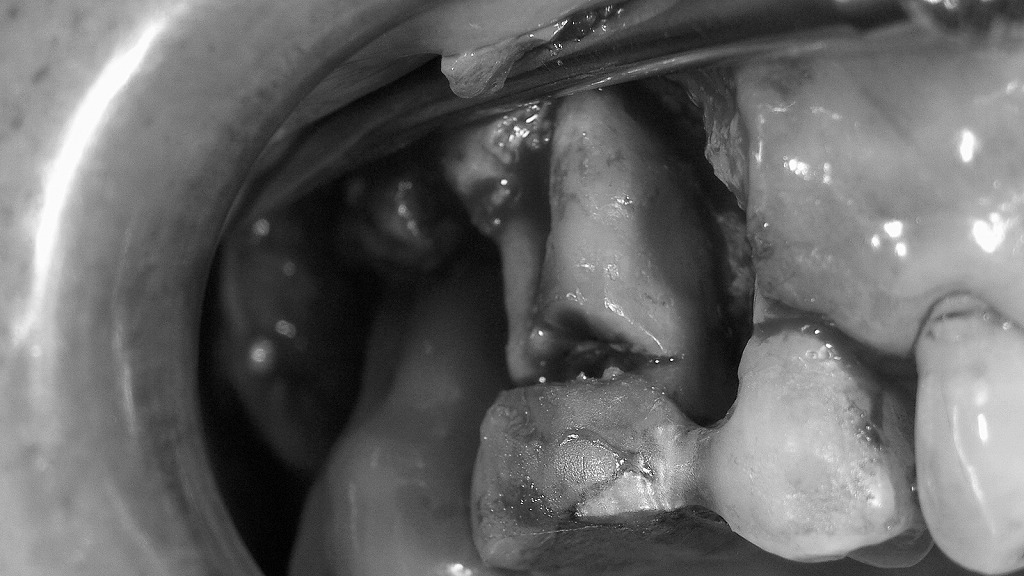

2. 歯周外科FOPの術前術後:炎症除去で歯周組織を整えた症例

🪥 予防と再発防止

- 定期的な歯科クリーニング(3〜4か月ごと)

- 正しいブラッシングとフロス・歯間ブラシの併用

- 噛み合わせや被せ物の適合確認も重要